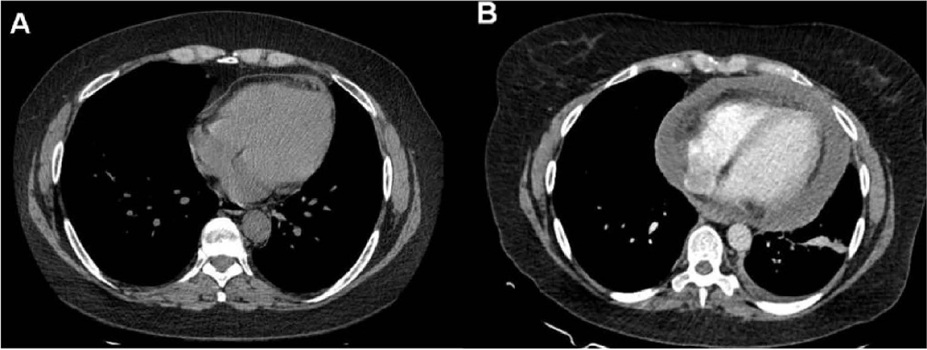

No que diz respeito à etiologia, a pericardite aguda por tuberculose é das mais prevalentes em nosso meio no contexto da aids. Neste trabalho relatamos o primeiro caso brasileiro com um surpreendente diagnóstico de pericardite por M. kansasii em função do levantamento tardio da cultura, destacando suas particularidades clínicas e laboratoriais (presuntivamente compatíveis com tuberculose), bem como as implicações terapêuticas deste resultado.